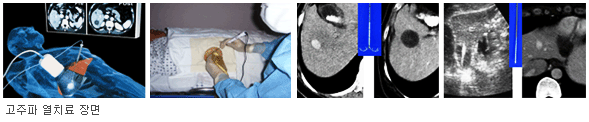

고주파 열치료법

고주파열치료 과정

▲ 고주파 열치료 치료전부터 치료 종료 후 5분까지